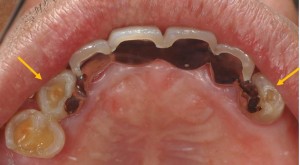

被せ物を外して土台の状態です。歯周ポケット検査は、手前(8mm、9mm)と奥側(5mm、5mm)です。要は、歯と歯の間から歯周病が進行してしまっています。

この歯は、抜歯適応かもしれませんが根が2つあるため1根のみ抜歯して頬側の根を残しました。

歯周病が進行してしまった歯、特に奥歯は根が2~3本あります。歯自体抜歯するのではなく、1/2もしくは1/3のみ抜歯することで歯を保存することもできます。

被せ物が装着された状態です。